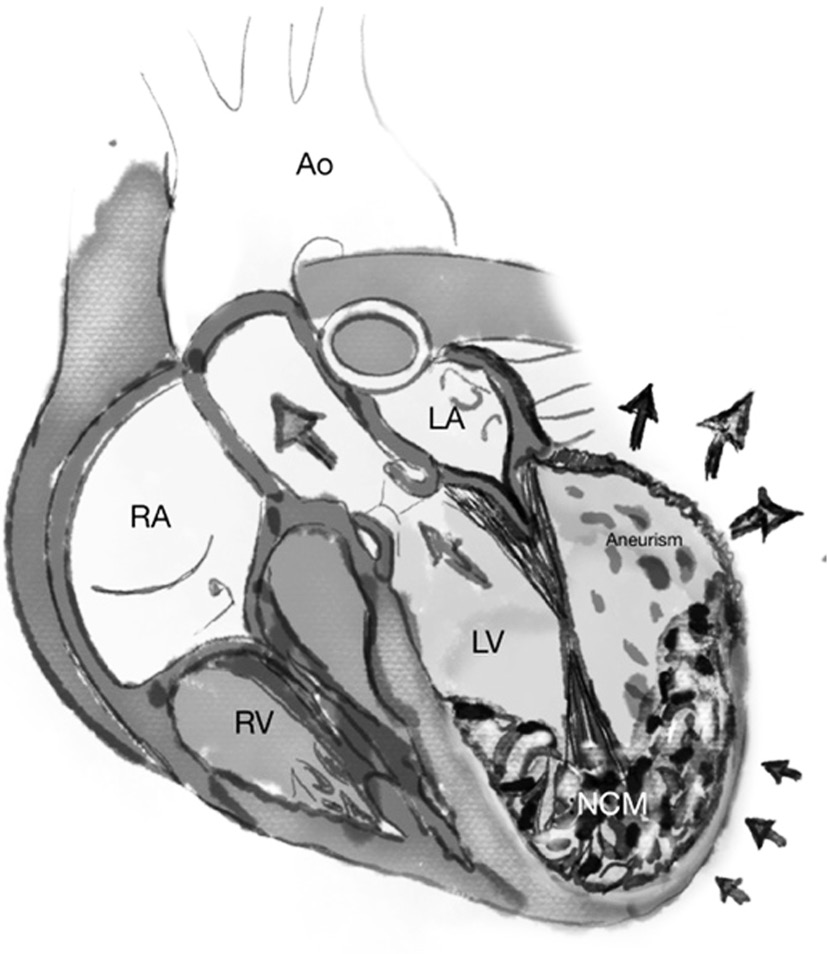

We encountered a rare case of LVNC with an LV aneurysm formation due to microcirculatory disorder. As demonstrated in our patient, the CMR criterion for diagnosing LVNC is a ratio of maximum thickness between the noncompaction and compaction layer of more than 2.3 in end-diastole, and the mass of trabeculated lv myocardium represents >25% of the total LV mass [10]. Myocardial delayed enhancement revealed scars along the aneurysm wall. Aneurysms have a large connection to the ventricular cavity (Figure 3), whereas diverticula are typically elongated and have a narrowed neck. Aneurysms are most commonly observed in the LV apex (28%) and the perivalvular area close to the mitral valve (49%). LV aneurysms are typically acquired following an acute myocardial infarction with systolic bulging and scar formation in the myocardium. Without knowledge of the patient’s medical history and coronary angiogram, acquired aneurysms are difficult to distinguish from congenital left ventricular aneurysms [11]. However, poor microcirculation is believed to be the etiology of aneurysm and scar formation in LVNC [12]. The aneurysm was unrelated to coronary artery territory because our patient’s coronary angiography was normal. In our case, an aneurysm appears to be acquired because her previous echocardiography analysis showed EF above 50%; subsequently, when symptoms of cardiac failure began to manifest, it began to diminish. Complications from ventricular aneurysms include intramural thrombus, cardiac output impairment, and aneurysm rupture.

Fig. 3. Non-compactness of the myocardium with a thin-walled aneurysm of the left ventricle. The aneurysm bulges from the basal portion of the anterior wall of the left ventricle during systole. Arrows show the direction of blood flow. Ao - aorta; LA - left atrium; LV - left ventricle; NCM—non-compact left ventricular myocardium; RA - right atrium; RV - right ventricle; aneurism - aneurysm.